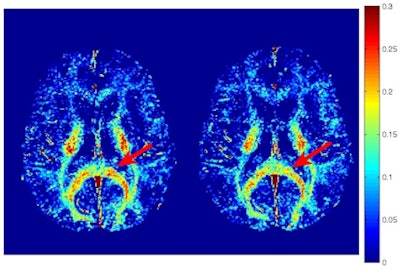

As one would expect, there also were no significant differences between preseason and postseasons scans of players who had no head injuries. Among the concussed athletes, the myelin water maps showed clusters of voxels with significantly reduced myelin water fraction -- a reduction of 6% (± 1.2%) -- two weeks after the injury, compared with baseline results.

Changes were most evident in the splenium of the corpus callosum, right posterior thalamic radiation, left superior corona radiata, left superior longitudinal fasciculus, and left posterior limb of the internal capsule.